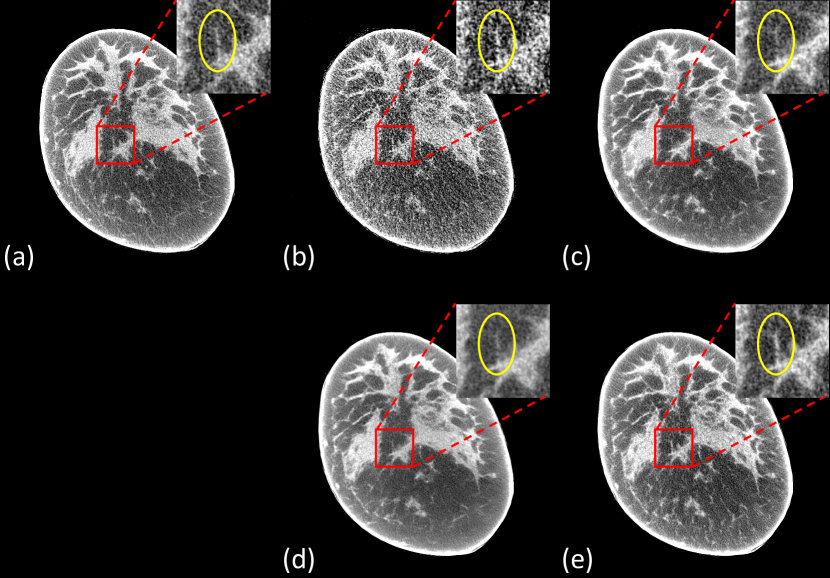

Refer to caption

Figure 6: Representative slice reconstructed using different methods for Koning dataset. (a) Ground-truth, (b) FDK from 75-view cone-beam data, (c) DEER-Lite, (d) DEER. The red boxes mark the Regions of Interest (ROIs). Yellow circles mark some subtle details in the ROIs. The display window is [-200, 200] HU. Note that the final reconstructions were post-processed to remove irrelevant structures outside the field of view.

III-D View-independent Network

As described in Section II, DEER utilized 𝒪(N2×Nv)𝒪superscript𝑁2subscript𝑁𝑣\mathcal{O}(N^{2}\times N_{v}) to improve quality of reconstructed images. However, the proposed ray-tracing idea could be trained with as few as 𝒪(N)𝒪𝑁\mathcal{O}(N) parameters. In this subsection, another DEER network (denoted as DEER-Lite) was built with 𝒪(N)𝒪𝑁\mathcal{O}(N) parameters by sharing all the parameters in the reconstruction part. To be specific, in DEER, projections at different angles are back-projected to the FOV using different sets of trainable parameters (e.g., projection data at 0superscript00^{\circ} are back-projected using trainable parameters at 0superscript00^{\circ}, and projection data at 90superscript9090^{\circ} are back-projected using trainable parameters at 90superscript9090^{\circ}). On the other hand, in DEER-Lite, projections at different angles are back-projected to the FOV using the same set of parameters. The amount of trainable parameters is reduced to 𝒪(N2)𝒪superscript𝑁2\mathcal{O}(N^{2}) by sharing the parameters at different view angles. To further reduce the number of trainable parameters to 𝒪(N)𝒪𝑁\mathcal{O}(N), parameters in DEER-Lite are also shared between all ray-tracing lines (i.e., all the points in the sinograms use the same set of parameters for back-projecting over the FOV). DEER is classified as a view-dependent network since different sets of parameters are used for different angles. DEER-Lite is a view-independent network since all projection angles use the same set of parameters.

DEER-Lite was trained in the same way as described in Section II, except DEER-Lite uses 𝒪(N)𝒪𝑁\mathcal{O}(N) parameters, while DEER uses 𝒪(N2×Nv)𝒪superscript𝑁2subscript𝑁𝑣\mathcal{O}(N^{2}\times N_{v}) parameters in the back-projection part. As shown in Fig. 6, a representative slice was selected to present the difference in reconstruction quality of DEER and DEER-Lite. The corresponding quantitative assessments are shown in Table III. Both networks demonstrate superior denoising performance. Even though DEER only shows slight improvements in terms of selected quantitative measurements, it demonstrates more stable and clinically-favorable reconstructions in certain testing patients. For example, in the red ROI of Fig. 6, DEER-Lite produces some fake features that do not exist in both ground-truth images and results produced by DEER. Moreover, these unreal features are visible throughout this image volume. One possible reason for this phenomenon in DEER-Lite is that, since the proposed network-based reconstruction algorithm is learning a revised back-projection mechanism, it learns to compensate for some noise and artifacts during the reconstruction. And because the parameters are shared in all views, these compensations may produce artifacts in other views. On the other hand, DEER does not have this problem because the parameters are view-dependent in the reconstruction part, and compensations at a specific angle will not affect back-projection at another angle. Lastly, since the back-projected profiles are rotated to the corresponding angles during reconstructions, and the involved interpolations can negatively affect the image quality, a view-dependent network provides more degrees of freedom to address this issue by learning different ray-tracing patterns using different sets of parameters.

Since the trainable parameters in DEER-Lite are view-independent, it can be applied to other numbers of views directly without further re-training. To show that DEER-Lite can be used for reconstructions in different few-view conditions, the network (which was trained on 75-view data) was tested for 30-view reconstructions. The testing details are the same as described above. First, few-view reconstructed volumes were produced from 30-view cone-beam projections using the FDK algorithm. Then, 200-view parallel-beam projections were estimated from the reconstructed volumes (we simulated 200-view parallel-beam projections instead of 150-view to show that DEER-Lite can handle other numbers of views directly). Note that because the reconstructed image from the back-projection part in DEER (and its variances) is a summation of back-projected profiles at different view angles, the magnitude of the learned reconstructed image will be changed with different numbers of views. Therefore, simple linear re-scaling is necessary to adjust the magnitude of the reconstructed image from the back-projection part according to the view number. Lastly, the trained DEER-Lite model, which was trained for 75-view reconstructions, was directly used to produce 30-view results. A representative slice is shown in Fig. 7. The reconstructed image is compared with the ground-truth image, the FDK result from 30-view cone-beam data, and the FBP result from simulated 200-view parallel-beam data. The corresponding quantitative measurements are shown in Table IV.

Figure 7: Representative slice reconstructed using different methods for Koning dataset for directly testing on 30-view data using a trained 75-view network. (a) Ground-truth, (b) FDK from 30-view cone-beam data, (c) FBP from 200-view simulated parallel-beam, (d) DEER-Lite. The display window is [-200, 200] HU. Note that the final reconstructions were post-processed to remove irrelevant structures outside the field of view.